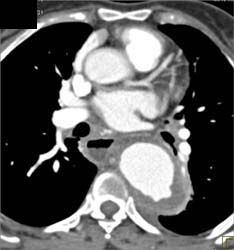

Diagnosis

Chest Wall Reconstruction With Hardware